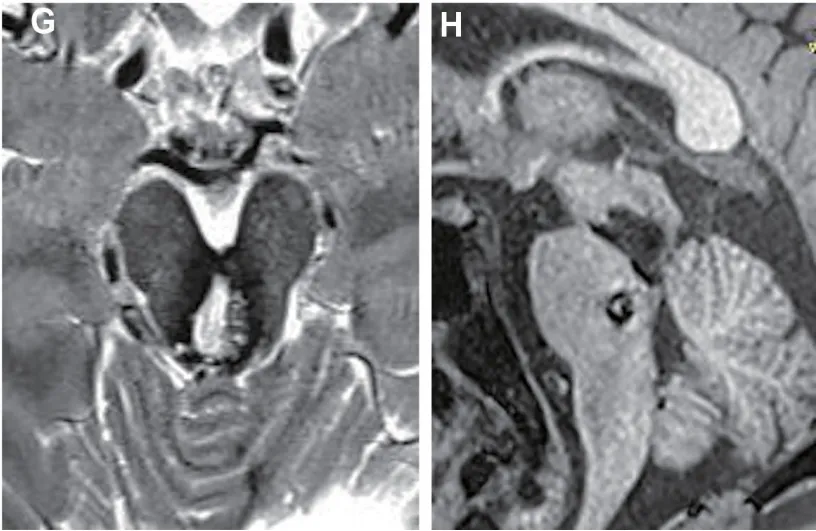

术后5个月轴位、矢状位磁共振成像,证实中脑海绵状畸形(MCM)完全切除。

术后5个月,决定性的时刻到来:复查磁共振成像。轴位和矢状位图像带来令人欣慰的结果——中脑的主病灶已被完全切除,切除区域恢复良好。而那个曾被黄色箭头标记的小卫星病灶,依然静静地待在脑桥原处,大小稳定,没有出血迹象。